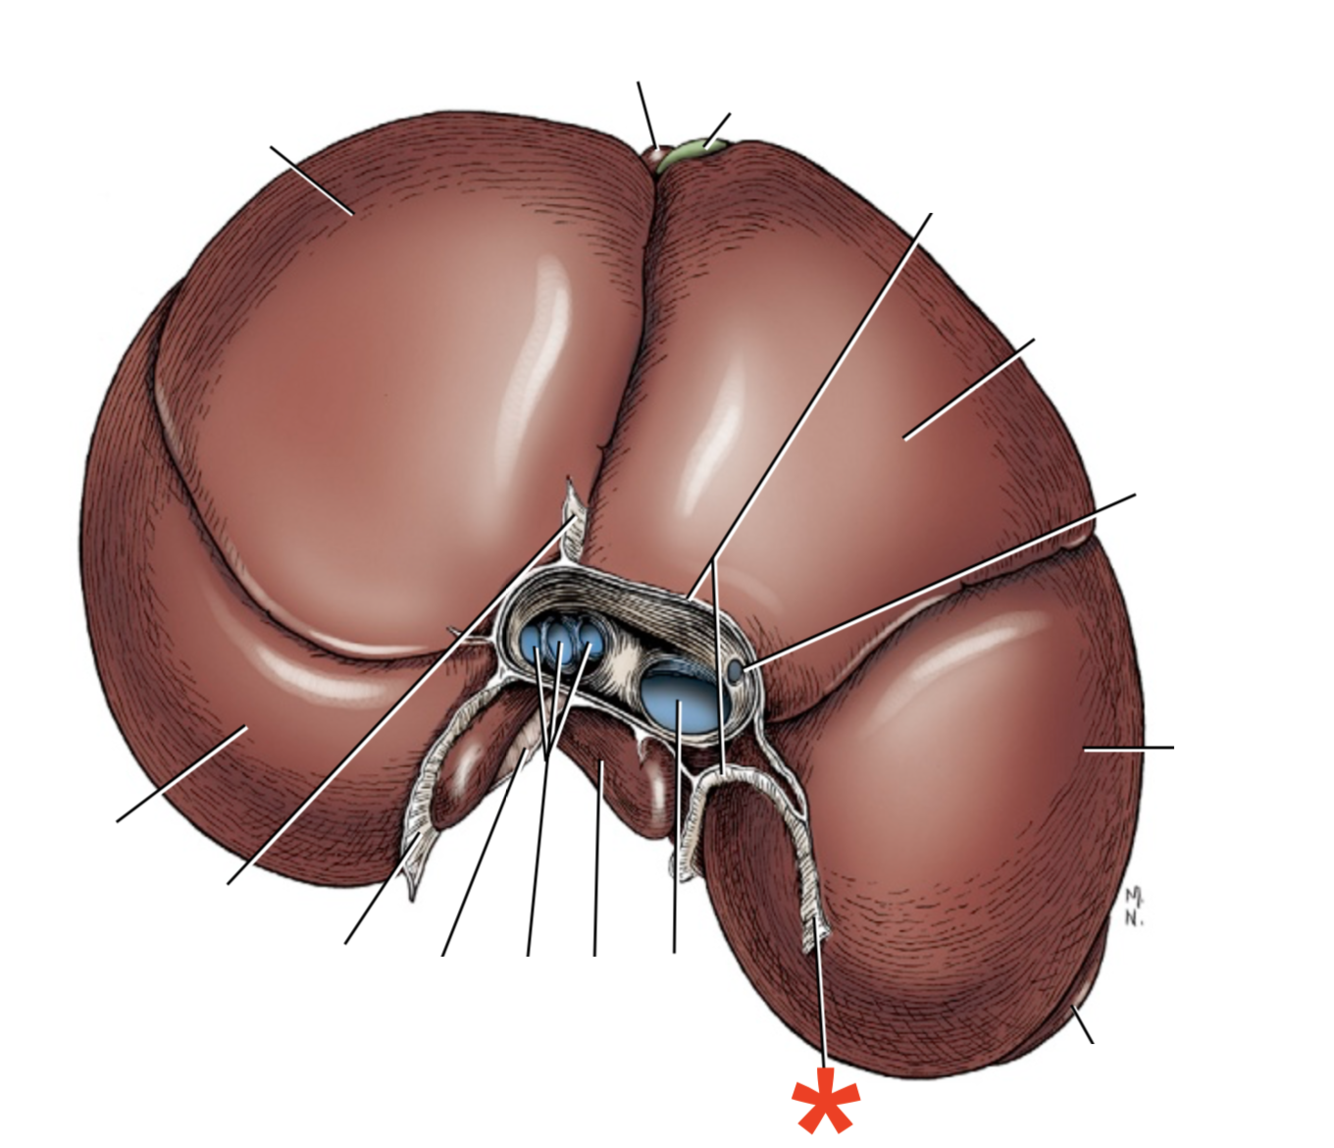

Facies diaphragmatica

What is shown? Give the Aspect

Liver of a Cat

Area nuda

- Not covered by serous membrane

The Caudate Process extends from the…

Lobus caudatus

The sharp-edged border of the liver is called…

Margo acutus

The blunt-edged border of the liver is called…

Margo obtusus

Ligg.falciformehepatiset tereshepatis

18

Lig. coronale hepatis

15

Lig. hepatogastrica

16

Lig. hepatoduodenalis

- Adjacent to ostium pyloricum

Lig. triangulare sinistrum

Lig. triangulare dextrum

Lig. hepatorenale